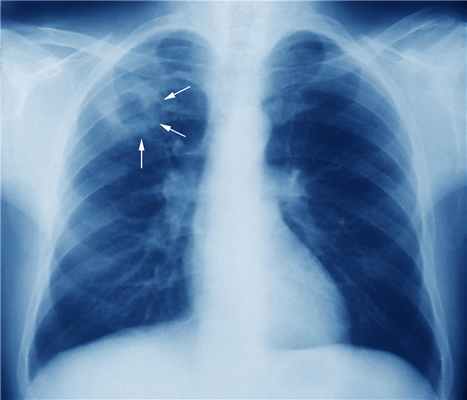

Требуется сделать рентгеновский снимок грудной клетки, который позволяет получить изображение лёгких. При лёгочной форме туберкулеза на снимке должны быть видны изменения во внешнем виде легких, например, образование рубцов.

Из-за того, что болезнь на начальных стадиях не проявляет себя, особое внимание уделяют профилактическим обследованиям. Для этого взрослые каждый год проходят флюорографию грудной клетки, а детям делают пробу Манту (туберкулиновую) или диаскинтест, направленные на выявление степени инфицированности организма туберкулезной палочкой и реактивность тканей. Есть также альтернативные исследования крови: T-SPOT тест и квантиферон-тест. Рентгенография позволяет выявить инфекцию не только в легких, а и в других органах. В случае необходимости проводят КТ.